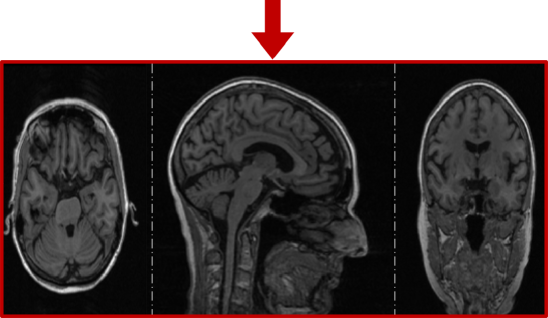

Figure 4: The MRI preprocessing pipeline depicted across three orthogonal views of 3D MRI images.

Data Preprocessing. Preprocessing is imperative in medical imaging registration, as discussed in Section III-A. Our MRI image preprocessing pipeline, illustrated in Fig. 4, consists of three essential steps: